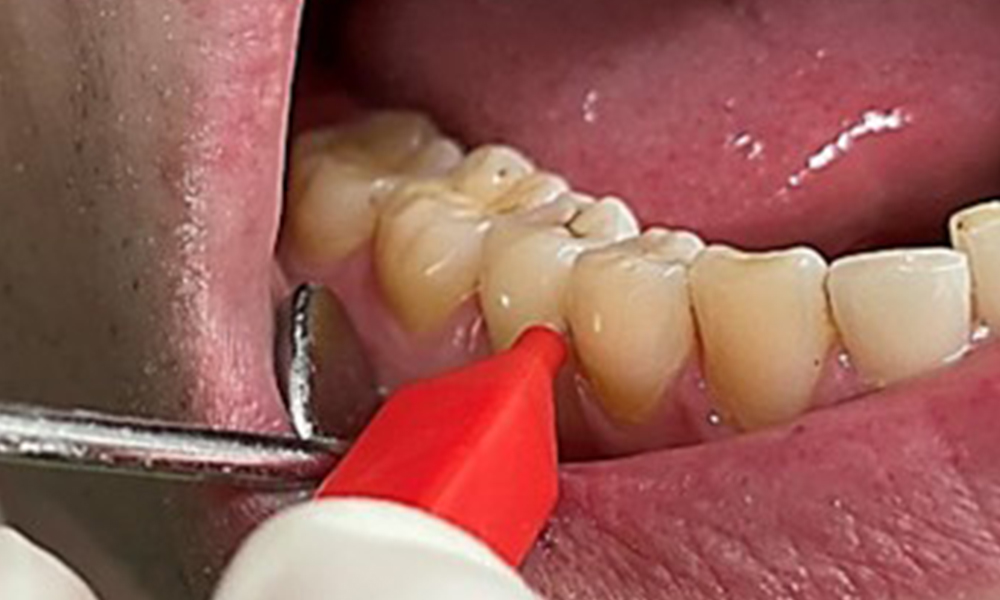

The objective would be to control disease risk by removing supragingival and subgingival biofilm. The instruments can be selected based on patient needs. First, calculus and any concretions must be removed using ultrasonic and/or manual instruments (Fig. 10).

Discolouration caused by nicotine and tea consumption can be removed easily using an air polisher (Fig. 11).

When using more abrasive powder, it is essential to work from a cervical to coronal direction and never point the outlet nozzle towards the gingiva to prevent potential emphysema. Good suction on the contralateral side is essential to reduce aerosol formation (Fig. 12).